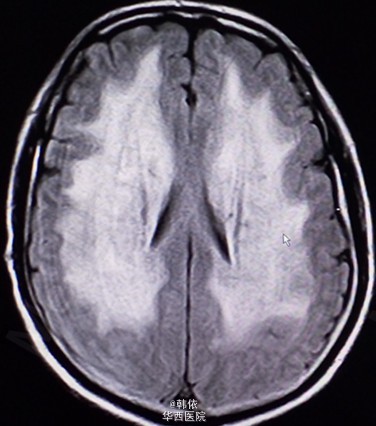

原创:青年男性,因“反复突发意识障碍1+月”入院,1+月前,患者感冒后突发意识障碍,呼之不应,随之出现四肢抽搐,双上肢屈曲、抽搐,双下肢强直,双眼向上凝视,牙关紧闭,小便失禁,无口吐白沫等,持续10+秒后意识恢复,不能回忆,急诊入当地医院治疗,行脑脊液、头部增强MRI等检查,考虑“痫性发作,病毒性脑膜炎”给予降颅内压、抗病毒等治疗,患者住院过程中出现一次右下肢抽动及多次小便失禁,治疗过程中感头部昏沉感,呈持续性,并出现饮水呛咳,治疗效果欠佳。既往患有高血压2+年,未治疗。长期农药接触史2+年。查体:神清,对答切题,高级神经活动正常,双瞳孔等大等圆3mm,对光反射灵敏。四肢肌力肌张力正常,左侧病理征(+),右侧病理征(-),余无特殊。辅助检查:头部MRI示:双侧基底节、双侧丘脑、脑干、双侧小脑及双侧侧脑室旁、双侧半卵圆中心对称性信号异常,考虑中毒性、代谢性疾患可能(见下图)。